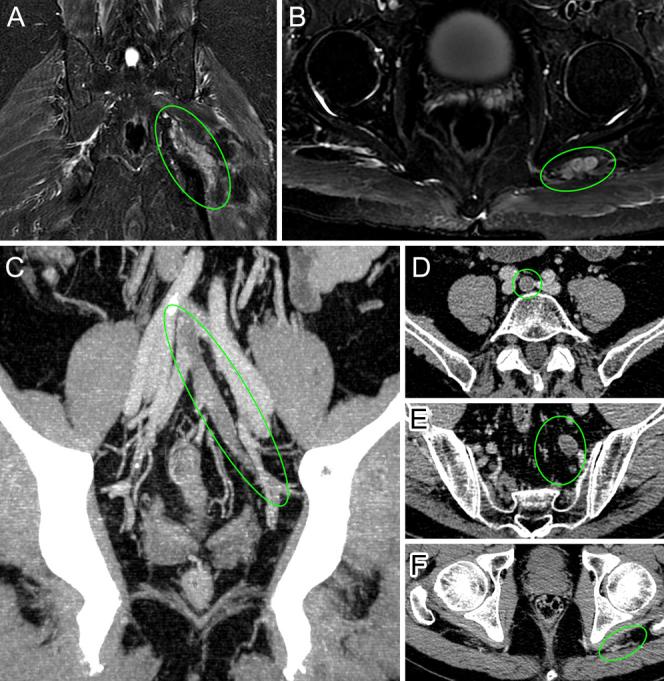

OBSERVATIONS

Pelvic magnetic resonance imaging uncovered varicose structures displacing the left sciatic nerve. Subsequent pelvic computed tomography angiography identified a remarkable finding-the lack of opacification in a left persistent sciatic vein ascending toward a left internal iliac vein, originating from a common internal iliac venous trunk-confirming a suspicion for deep venous thrombosis. These findings represented not 1, but 2, extremely rare and distinct variants in the venous anatomy. The authors promptly initiated anticoagulant therapy and tailored pain management strategies, observing progressive thrombosis resolution on follow-up imaging.

观察结果

盆腔磁共振成像发现曲张结构压迫左侧坐骨神经。随后的盆腔计算机断层扫描血管造影发现了一个显著结果——一条起源于髂总静脉干、向上通向左髂内静脉的左侧坐骨神经持续静脉不显影,证实怀疑为深静脉血栓形成。这些发现并非一种,而是两种极其罕见且不同的静脉解剖变异。作者立即开始抗凝治疗并制定了疼痛管理策略,在后续成像中观察到血栓逐渐溶解。